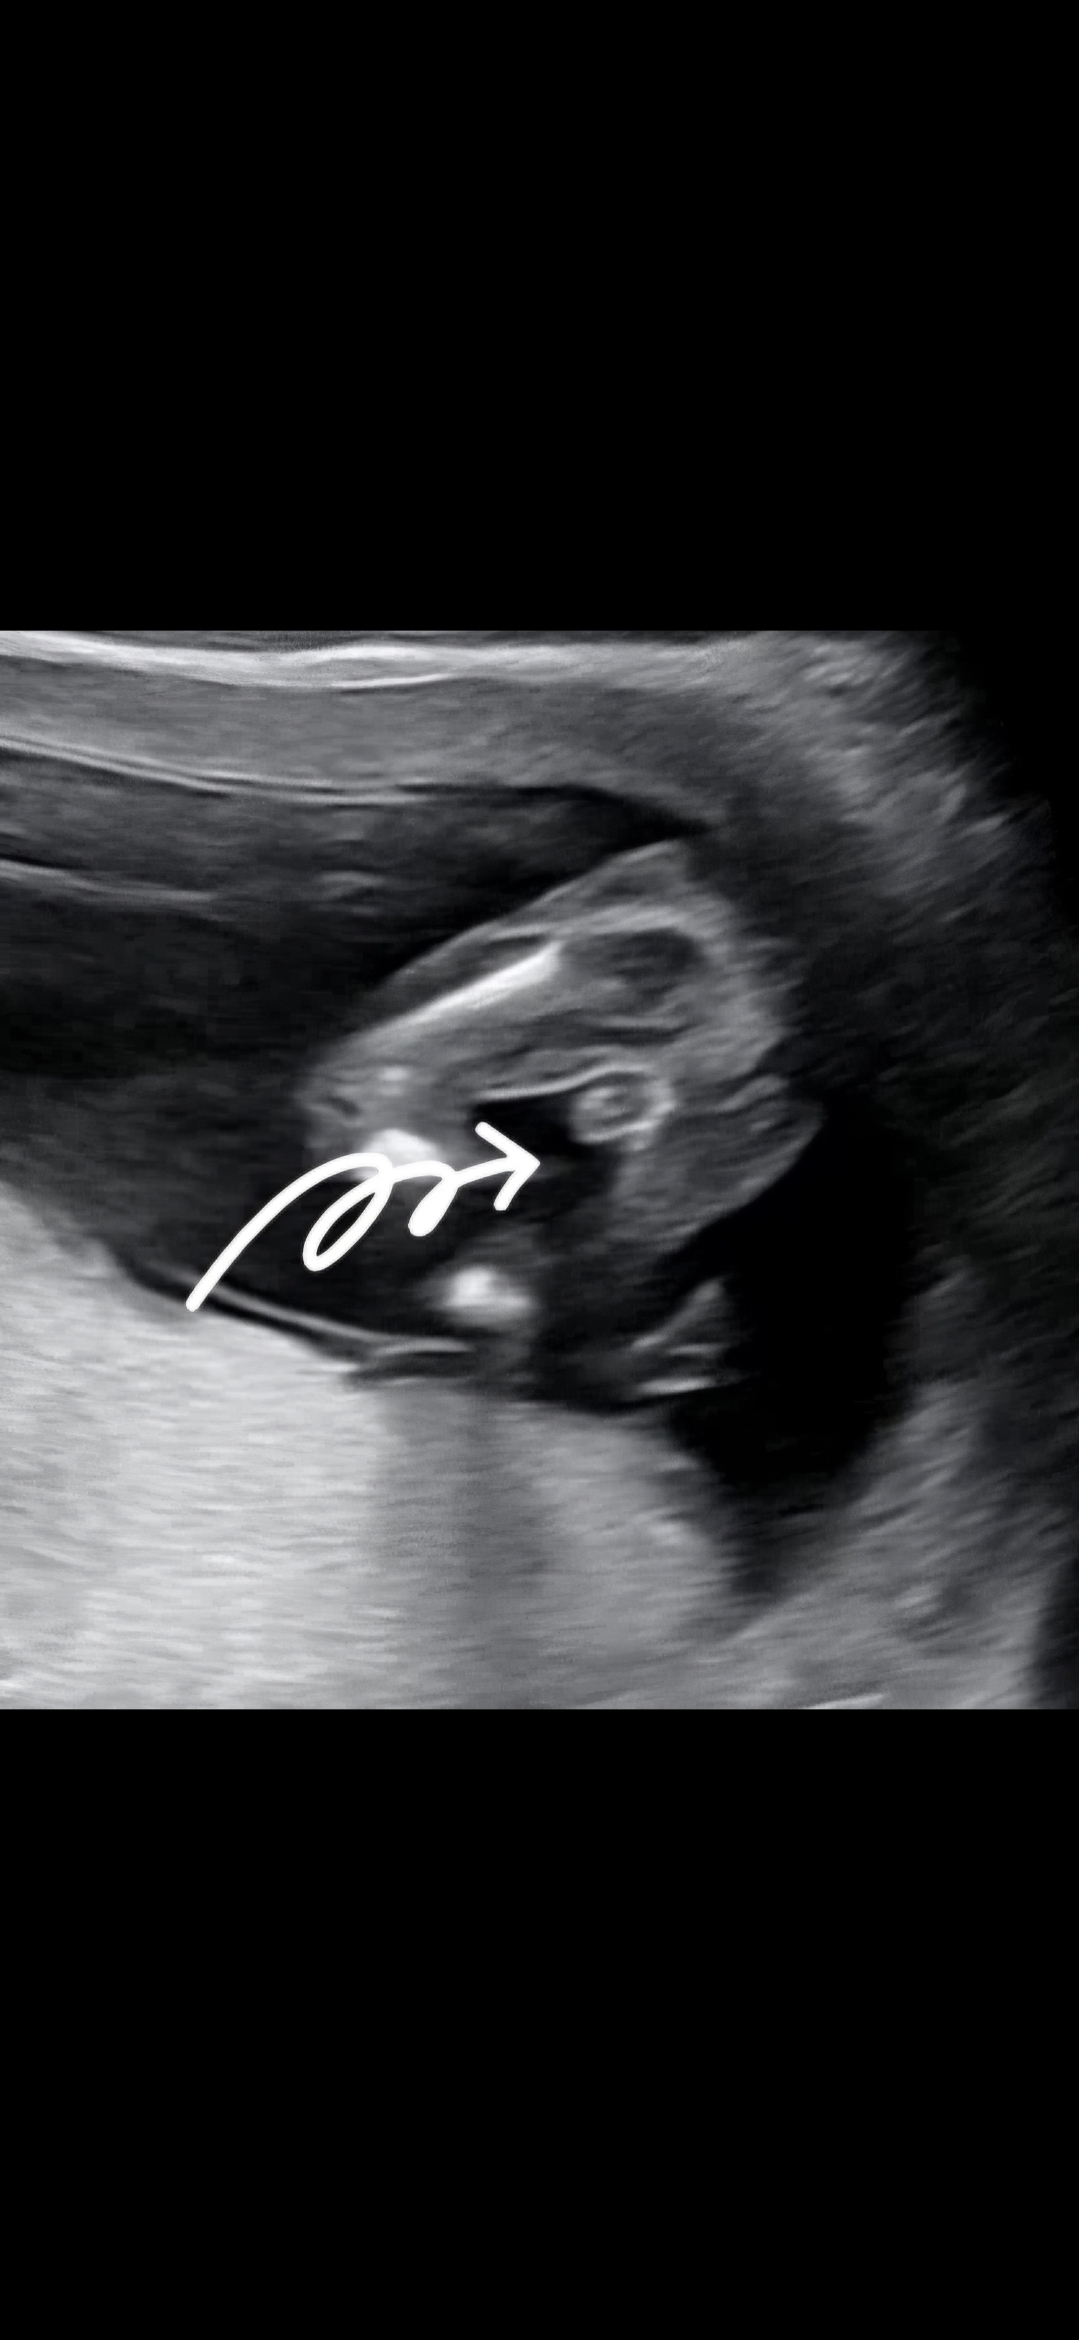

우리 아가 성별 확정일까요! 14주 1일

14주 1일차 사진인데, 아빠쪽인것 같다구 하시네용ㅎㅎㅎㅎ 심장소리 완전 말발굽, AI빌리 각도법도 딸로 나왔는데 아들딸 상관없으나 쪼끔 놀라구왔어용

왕자님 맞는거같아용